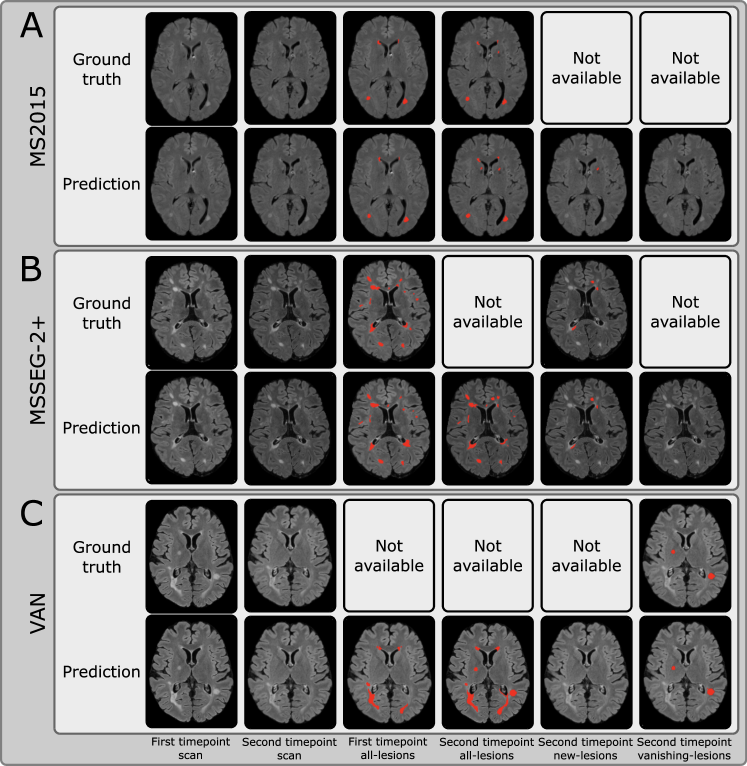

SegHeD+ is a model capable of performing three segmentation tasks, namely all-lesion, new lesion and vanishing lesion segmentations. We assess its performance across multiple tasks and compare it with state-of-the-art task-specific segmentation approaches such as nnU-net [13], nnFormer [46], UNETR [47], a recent method for learning from heterogeneous data called CoactSeg [15], a previous iteration of this work, SegHeD [26], which does not feature LesionMix augmentation, and methods specifically tailored for new lesion segmentation [23, 14], as presented in Table 3. It has to be noted that only SegHeD and SegHeD+ are capable of performing all three tasks simultaneously. The task-specific SOTA methods undergo two rounds of training: one for the all-lesion segmentation task using the MS2015 and MS2016 datasets, and another for the new-lesion segmentation task using the MSSEG-2 dataset. CoactSeg [15] is trained only once, as it can handle data input and inference for all-lesion and new-lesion segmentation. For new lesion segmentation with the MSSEG-2 dataset, we present Dice scores for MedICL [48], Basaran [14], and the average score from four human experts, denoted as “Avg. of Experts", officially reported by the challenge organizers [4]. The “Avg. of Experts" can be regarded as the upper bound performance for new-lesion segmentation on MSSEG-2. Additionally, we include lesion-wise F1F_{1} scores in Table 4, as per the guidelines of the MSSEG-2 challenge. Example segmentations are compared in Figure 4, with more examples provided in the Figure 5.

Figure 5: SegHeD+ is capable of simultaneous multi-task segmentation (Rows 3 to 6). Some tasks do not show new/vanishing-lesions predictions as they are not present at the given slice. “Not available" denotes no ground truth annotation for comparison. A: Dataset where all-lesion labels are available for first and second timepoints. B: Dataset where first timepoint all-lesion label and second timepoint new-lesion label are available. C: Dataset where second timepoint vanishing-lesion label is available.